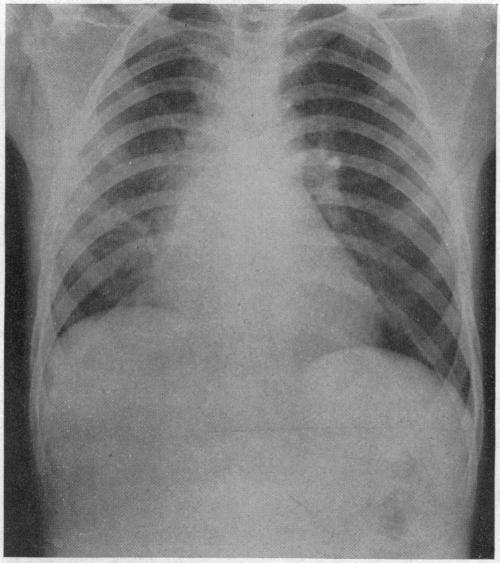

ACUTE MASSIVE COLLAPSE OF THE LUNGS: A DISCUSSION OF ITS MECHANISM AND OF ITS RELATION TO FOREIGN BODIES IN THE BRONCHI AND POST-OPERATIVE COMPLICATIONS.

Ann Surg. 1925 Sep;82(3):364-89. doi: 10.1097/00000658-192509010-00005.